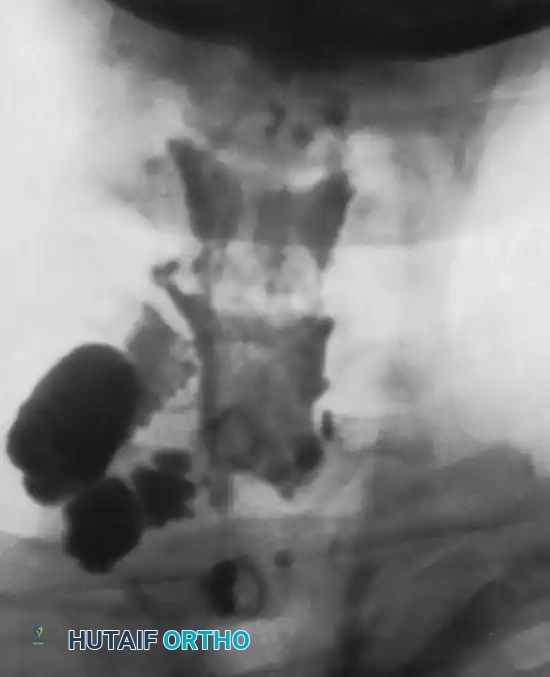

- CT Myelography: Highly sensitive for detecting pseudomeningoceles (extravasation of contrast through an empty dural root sleeve), which strongly correlates with root avulsion.